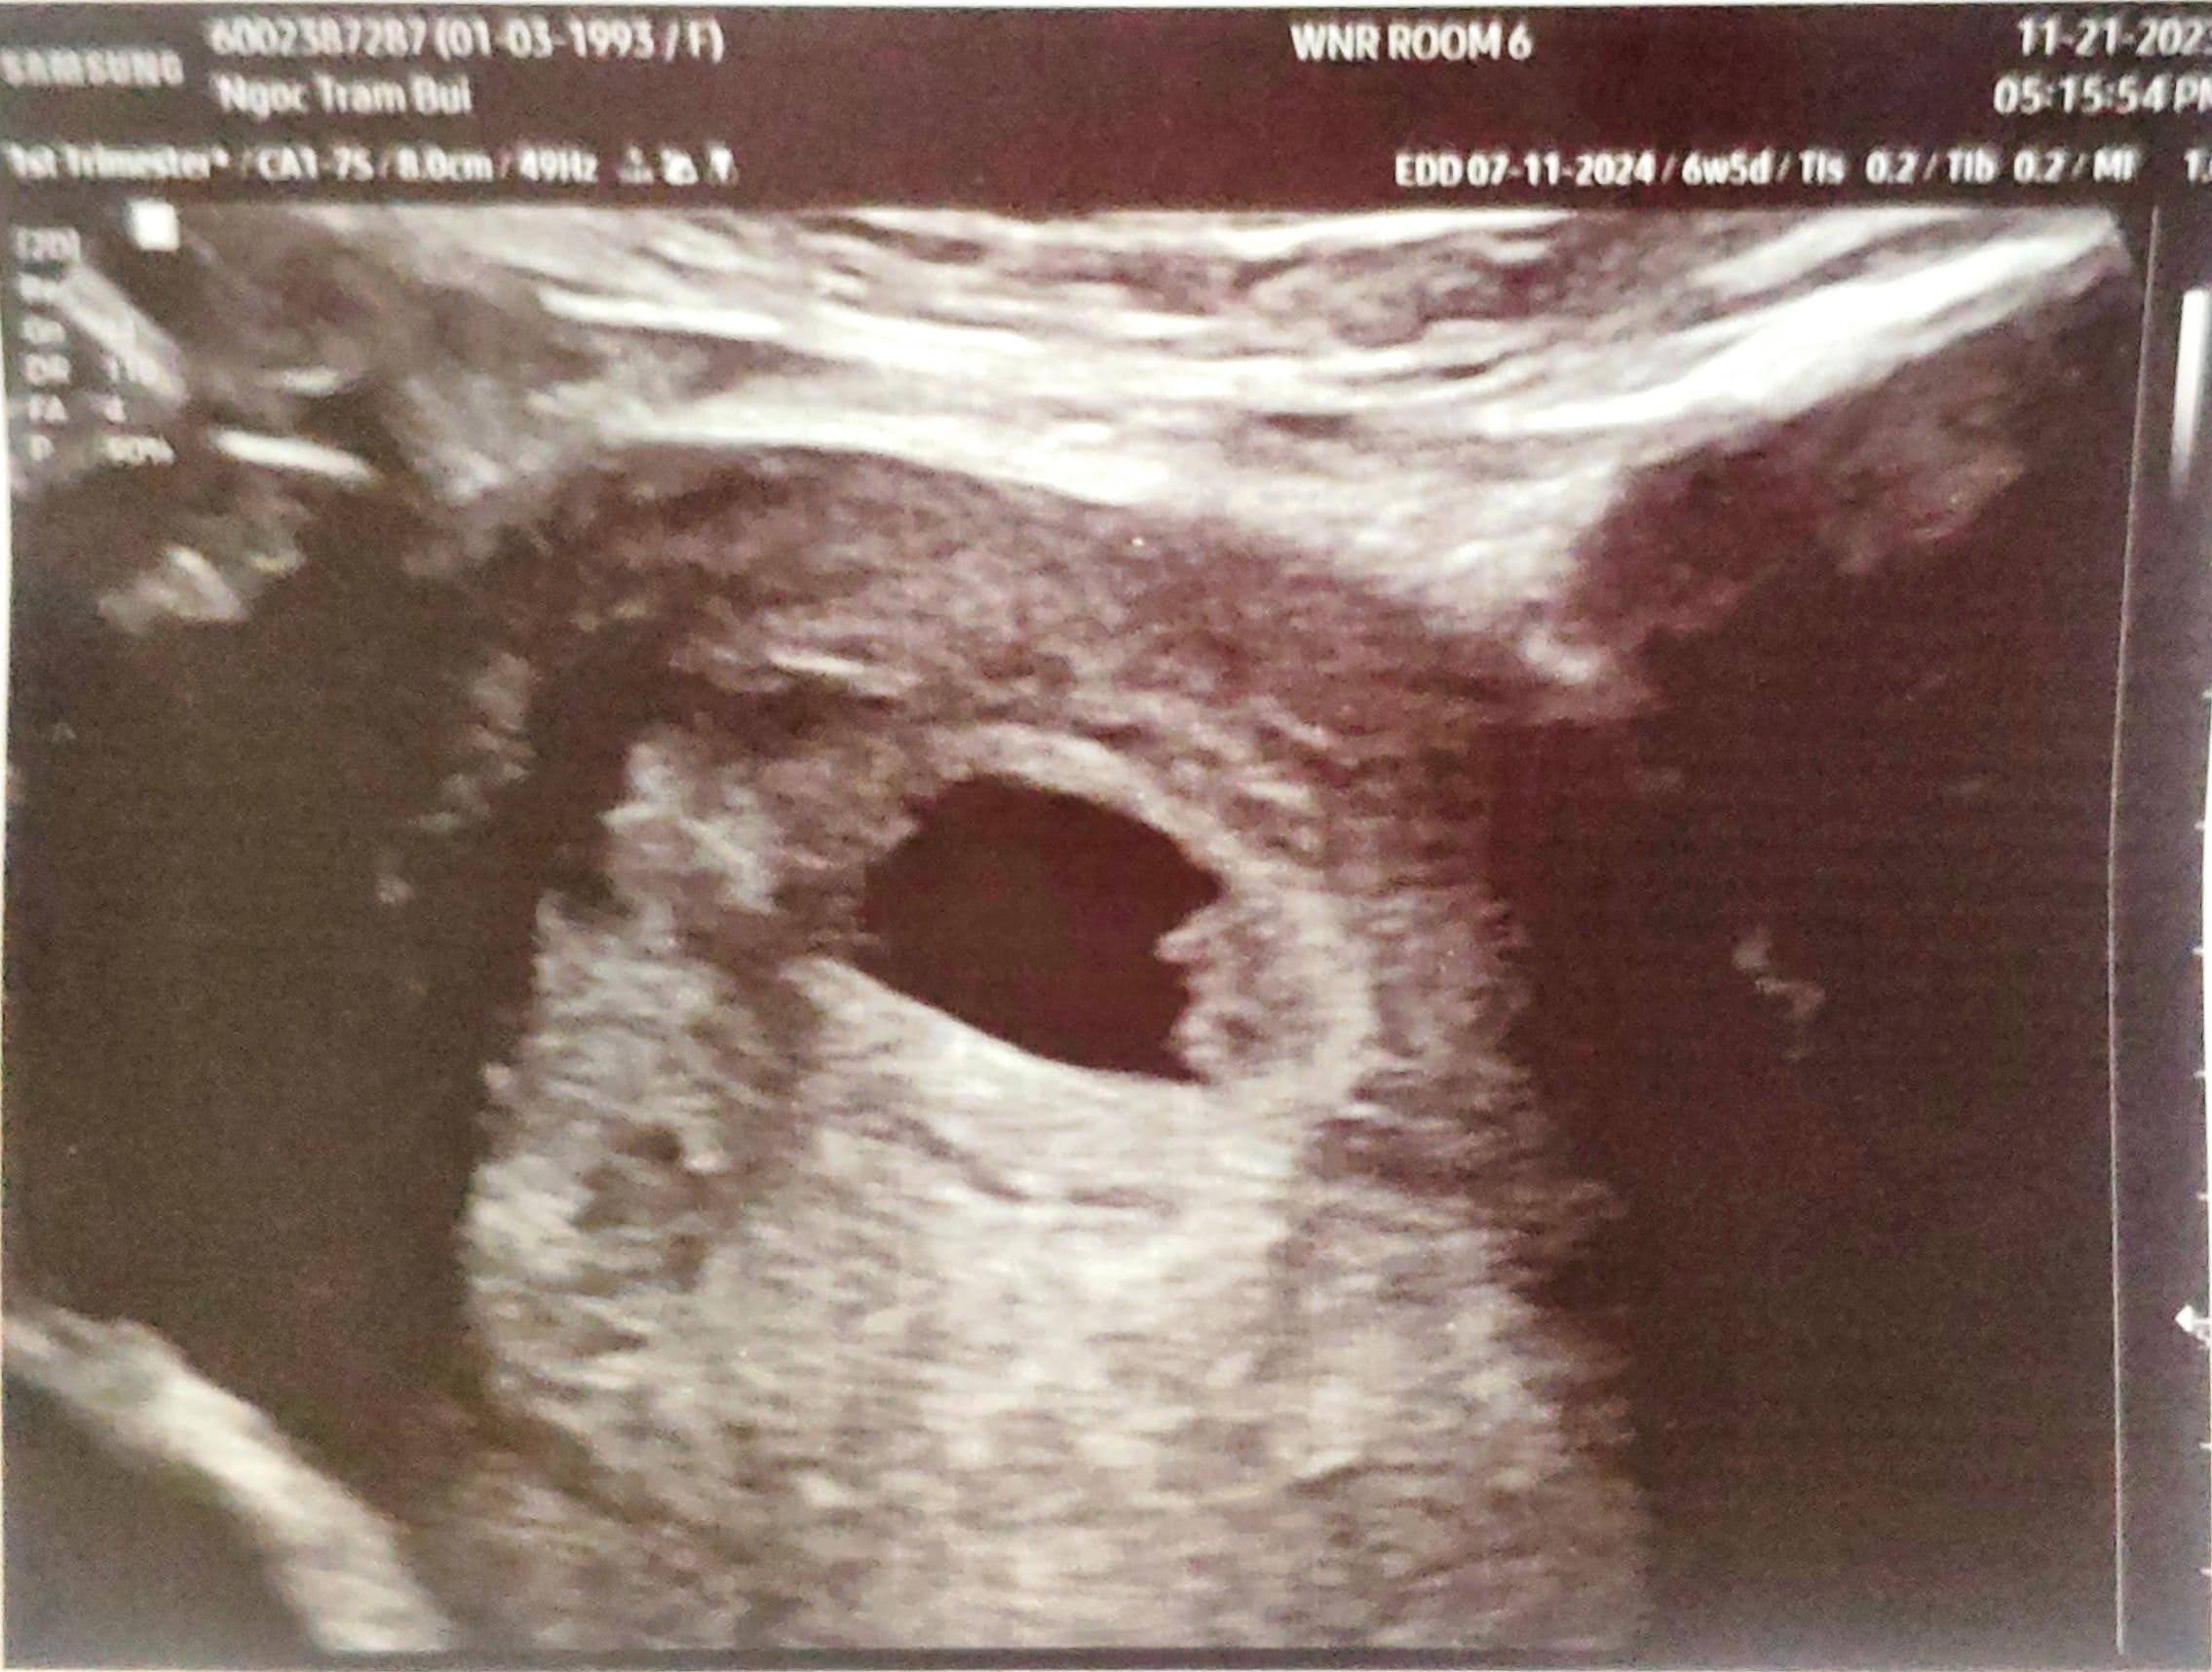

Đi ultrasound

7 Nov 2023

Một ngày mà hoàn tất xét nghiệm máu và siêu âm. Niềm vui khôn xiết vì đã thấy được tim thai